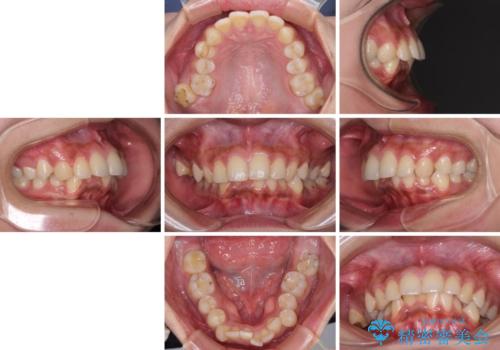

深い咬み合わせと前歯のデコボコ インビザラインによる矯正治療

- 前歯のデコボコと、食いしばりやすい咬み合わせを気にして来院された患者様です。

骨格的に下顎骨が左側に偏位しており、インビザラインでの矯正治療では奥歯の咬みにくさが残る仕上がりが懸念されましたが、新幹線での通院となるため、来院回数の少ないインビザラインでの治療を希望されました。

リスクをご説明した上で、インビザラインにより気になっている叢生と深い咬み合わせを改善していくこととしました。

治療途中では、左右ともに奥歯が咬みにくい状態が続き、問題なく噛めるようになるまでに長期間を要しました。

一方で、デコボコや下顎の前歯が隠れてしまうほどの深い咬み合わせはしっかりと改善されました。